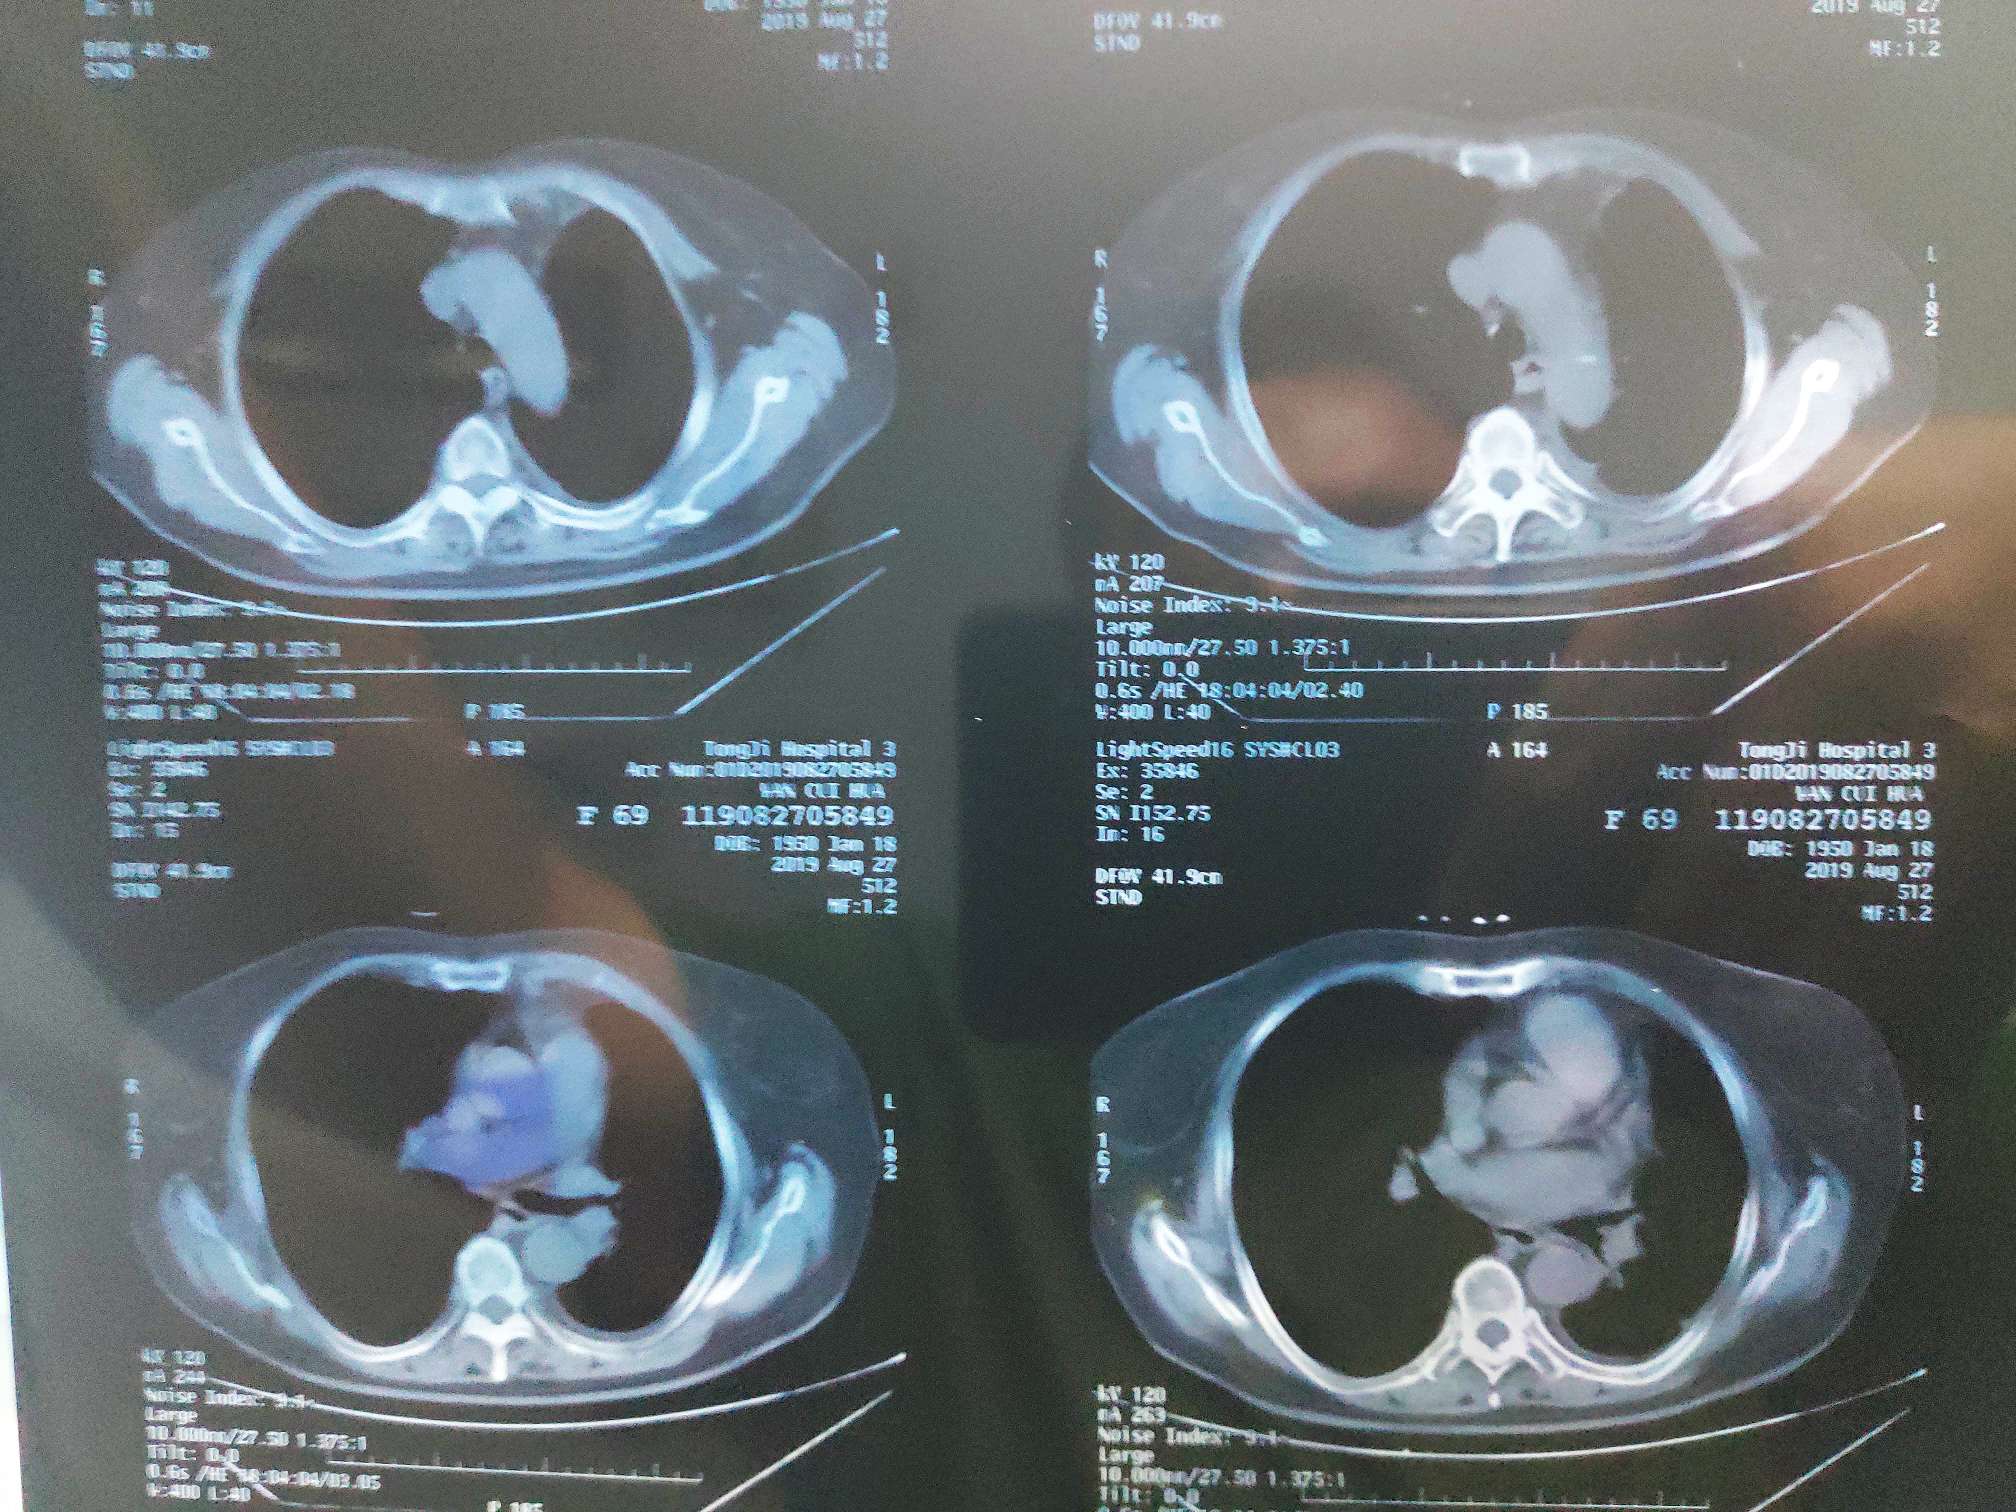

8.29二化评估全面缩小

肺部膨胀不全开始明显缓解(蓝色箭头),肺部炎症好转,医生说因为化疗使用的是多西他赛单药,二化出现这么明显好转,应该是pd1联合的效果,单药多西他赛应该不会这么明显,建议继续治疗,我提出能否下次开始单药pd1治疗,医生不赞同,说等化疗不耐受再尝试pd1单药。

三化前CT